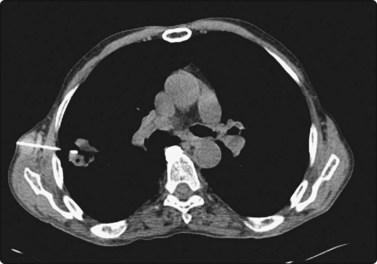

CT scanning

There are very few areas of the body which cannot be biopsied under CT control, and extremely small lesions can be sampled. Focal masses of several millimeters within the lung and skull base (Fig. 3.2) can be biopsied and retroperitoneal biopsies are limited only by availability of needles long enough to traverse the abdomen of large patients. Traversing with fine needles offers fewer risks compared with the larger-caliber needles.7 CT gantry tilt also further facilitates lesion access where appropriate.

image image

Fig. 3.2 (A) Circular low dense lesion right retropharyngeal node in a patient post right parotidectomy and radiotherapy for parotid squamous cell carcinoma. (B) Coaxial fine needle aspiration biopsy technique under CT control confirmed nodal recurrence. The utility of CT biopsy techniques and fine needle aspiration biopsy helped direct this patient’s management.